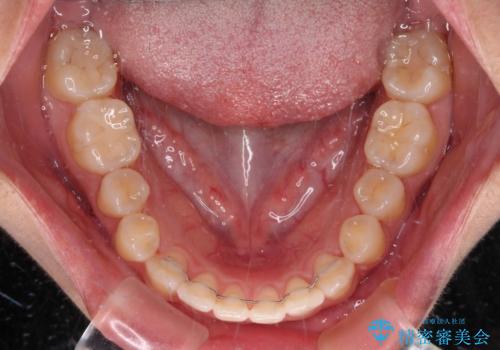

- 上下の前歯が非接触であることと、それに伴う口元の閉じにくさを気にして来院された患者様です。

奥歯の咬み合わせを見ると、上顎が下顎に対して相対的に前方にありました。

口元の閉じにくさを改善するためには、上顎臼歯を後方に移動させた咬み合わせにする必要があります。

インビザライン単体で改善することも可能ですが、達成する可能性が高くないため、カリエールディスタライザーという補助装置を併用して、より確実性を上げることとしました。

奥歯の咬み合わせを改善しながら、並行してインビザラインで歯列を整えることとしました。